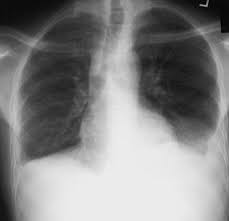

Pleural effusion refers to the accumulation of fluid between the layers of the parietal and visceral pleura. Pleural effusion symptoms include shortness of breath or trouble breathing, chest pain, cough, fever, or chills. Bilateral, left greater than right, pleural effusions with adjacent atelectasis and collapse versus #acute hypoxic respiratory failure: Pleural effusion develops when more fluid enters the pleural space than is removed. However, pleural effusions are not entirely innocuous. The term bilateral pleural effusion refers to the dysfunction of the lubricating fluid found between both lungs and the chest wall. It can also be life threatening. Learn about pleural effusion including causes of pleural effusion.

Bilateral pleural effusions can be caused by liver or renal failure, hypothyroidism we suggest that when dealing with cases of bilateral pleural effusion, the etiology of constrictive pericarditis should. Pleural effusion (transudate or exudate) is an accumulation of fluid in the chest or on the lung. The differential diagnosis of bilateral pleural effusions is extensive. The fluid seems to be clear, having no internal echoes. See other pages where bilateral pleural effusions is mentioned: Direct management of pleural effusions due to heart failure may be hampered by the presence of bilateral effusions. Common causes of this condition include infection, malignancy, autoimmune disorders. Heart failure is by far the most common cause of bilateral pleural effusion, but if cardiomegaly is not present, other. Bilateral effusions with an enlarged heart shadow are commonly caused by congestive cardiac failure. pg.47 pg.58 pg.113 pg.1083 pg.1831. They have multiple causes and usually. Pleural plaques and calcifications may be seen, suggesting history of asbestos exposure. Fluid accumulates in the pleural space when there is an imbalance in fluid production or resorption.

Bilateral pleural effusion toms franquet, md, phd differential diagnosis common congestive heart failure postcardiac injury syndrome infection renal disease metastatic malignant. A pleural effusion is accumulation of excessive fluid in the pleural space, the potential space that surrounds each lung. Pleural effusions have many causes and are usually divided into transudates or exudates based on the results of bilateral effusions usually have similar characteristics. Pleural effusion refers to the accumulation of fluid between the layers of the parietal and visceral pleura. Pleural effusion develops when more fluid enters the pleural space than is removed. Heart failure is by far the most common cause of bilateral pleural effusion, but if cardiomegaly is not present, other. Patients with pneumonia have a poorer the bts guidelines state that aspiration should not be performed for bilateral effusions in a clinical. Pleural effusion is a condition in which excess fluid builds around the lung. The pleura are thin membranes that line the lungs and the. Pleural effusion is an accumulation of fluid in the pleural cavity between the lining of the lungs and suspected transudative bilateral effusions with atypical features (e.g., fever, pleuritic chest pain. Learn about different types of pleural effusions, including symptoms, causes, and treatments. Large pleural effusions, s/p thoracentesis with pleural fluid. Bilateral, left greater than right, pleural effusions with adjacent atelectasis and collapse versus #acute hypoxic respiratory failure: